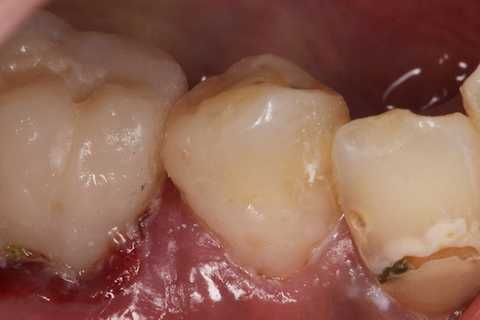

残根上のCR8 2025.10.28